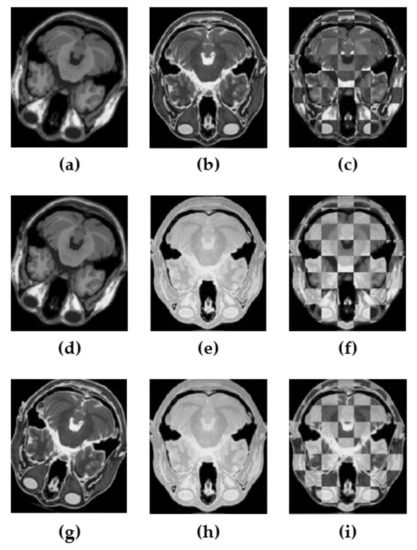

miRID: Multi-Modal Image Registration Using Modality-Independent and Rotation-Invariant Descriptor

Axiomatically, symmetry is a fundamental property of mathematical functions defining similarity measures, where similarity measures are important tools in many areas of computer science, including machine learning and image processing. In this paper, we investigate a new technique to measure the similarity between two images, a fixed image and a moving image, in multi-modal image registration (MIR). MIR in medical image processing is essential and useful in diagnosis and therapy guidance, but still a very challenging task due to the lack of robustness against the rotational variance in the image transformation process. Our investigation leads to a novel, local self-similarity descriptor, called the modality-independent and rotation-invariant descriptor (miRID). By relying on the mean of the intensity values, an miRID is simply computable and can effectively handle the complicated intensity relationship between multi-modal images. Moreover, it can also overcome the problem of rotational variance by sorting the numerical values, each of which is the absolute difference between each pixel’s intensity and the mean of all pixel intensities within a patch of the image. The experimental result shows that our method outperforms others in both multi-modal rigid and non-rigid image registrations. Full article